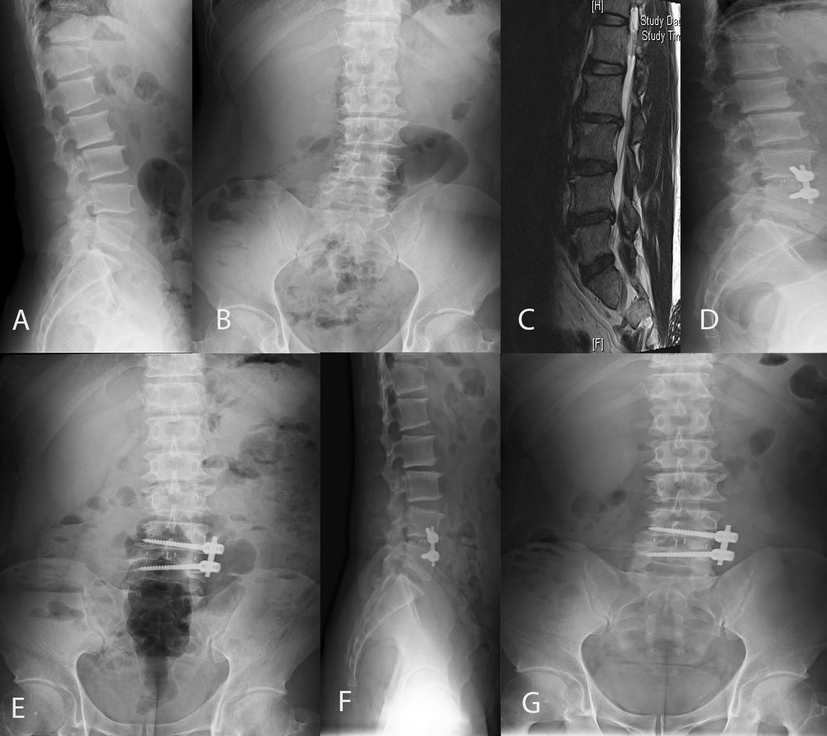

Vertebral body and disc morphometry of spinal  radiograph

The central concern of my writing is not to advocate for a practice around negative thoughts nor reinforcing negative language to self. Instead the problem is when we accept a single conception about a human experience or process like listening, we begin to believe it is one dimensional. Instead of looking at it like our spine, it is multidimensional. Our spine is often categorized as fragile and that we should stand up straight and pull our shoulders back for better posture. We neglect that the spine was not meant to be a straight vertical figure and that a healthy spine has an “s” shape curve for a reason. A true neutral spine has some degree of roundness at the upper back allowing the scapula to move freely so that it can sit on our rib cage. To create an optimal guiding and function but if we constantly absorb the idea that our backs need to be straight we condition ourselves to limit movement in the scapula and that compromises shoulder mobility over time. The curvature of our spine has a responsibility to make us stronger individuals and more reluctant to be capable of moving through the world in a certain way. The spine that maintains our body and the connection to our body isn’t straight, similar to how we perceive listening. It isn’t just hearing, it’s multidimensional. It is a state of experiencing and connecting and relating to ourselves and others that is fundamental to our being. For the purpose of this essay I will use the definition of listening by Wolvin and Coakley, as a process. They emphasize that listening is an active process of selecting, attending to, understanding and remembering auditory messages. Like the communication process, listening has cognitive, behavioral, and relational elements and doesn’t unfold in a linear, step-by-step fashion. While there is no consensus about what listening is; one theme remains abundantly consistent: listening is essential to our wellbeing and every aspect of it. Our relationship and discernment of ourselves depend on it. My hope, through this essay, is that you will learn how the western prevalent misconceptions about listening ruins the process in how we relate to one another and why language is failing us to overcome it.